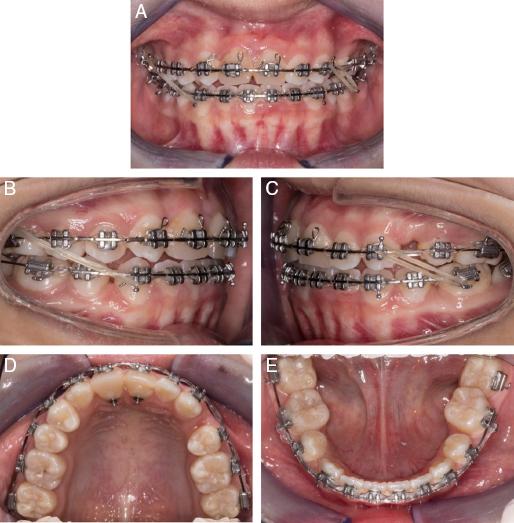

Orthodontic treatment began 6 months after the transplantation. Upper and lower pre-adjusted fixed appliances (MBT prescription, 0.022˝ × 0.028˝ slot; 3MTM Unitek Gemini) were placed. Once in 0.019˝ × 0.025˝ stainless steel wires, space closure was performed to mesialise the transplanted tooth towards the midline. Full-time Class II (3.5 oz, ¼˝) elastics were bilaterally added to support overjet reduction. Nickel-titanium coil springs were placed between #13 and #23 to prepare spaces for composite build-up (Figure 4A-E). The transplanted tooth was reshaped with selective enamel grinding on the palatal cusp to avoid heavy occlusal forces. Finishing step bends were placed to idealise the gingival margins of the transplanted teeth and increase palatal root torque on the upper incisors. The total orthodontic treatment time was 29 months. Following removal of the orthodontic appliances, the prosthodontist was able to carry out composite resin build-ups on #13 – #23. The patient was fitted with an upper fixed bonded retainer and asked to wear upper and lower vacuum-formed retainers on a night-time basis (Figure 5A-G).

(A–E) Midtreatment intra-oral photographs.